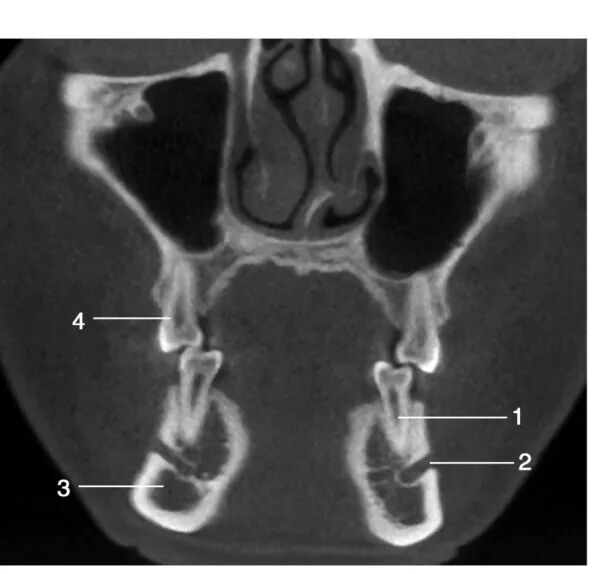

经下颌第三磨牙处层面冠状位图像

1.左下第三磨牙 ; 2.下颌神经管; 3.喙突 ;4.下颌升支